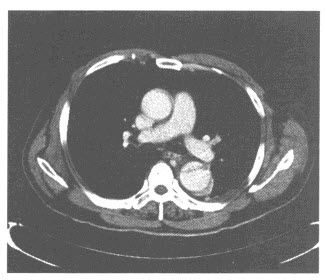

D.肾炎

男,58岁,头痛、恶心、行走不稳,肺和脑CT检查如图,最可能的诊断为()

A.星形细胞瘤

B.脑脓肿

C.肺癌脑转移